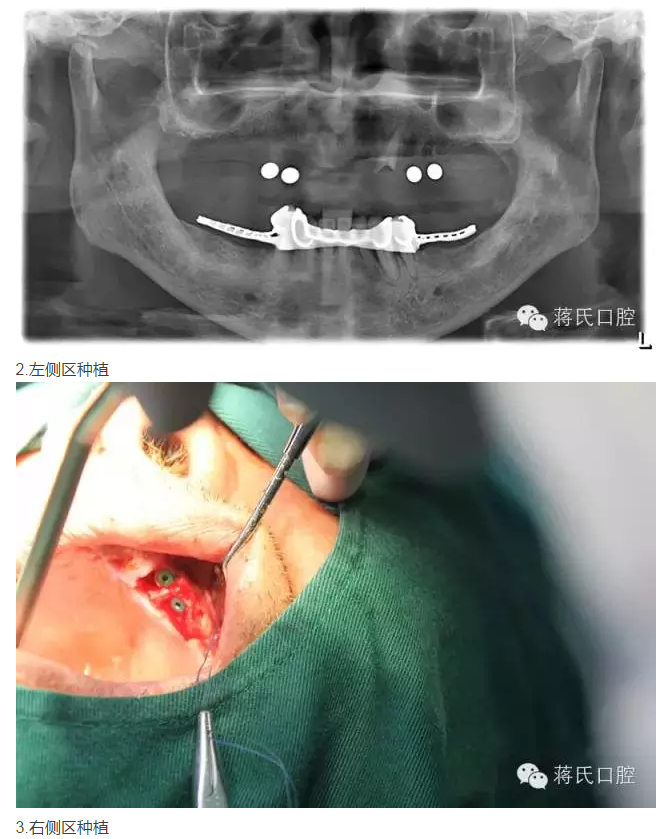

修復(fù)前全景片

3兩側(cè)四五區(qū)種植共4顆

4活動義齒雙重冠修復(fù)

5去除上頜基托